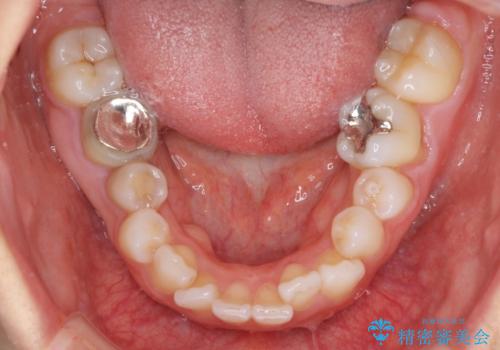

- 口元の閉じにくさと、奥歯の咬み合わせを気にして来院された患者様です。

左下の大臼歯2本が顕著に舌側に傾斜しているため、まずは奥歯の咬み合わせを改善をし、その後上下左右の第1小臼歯4本を抜歯することで口元を引っ込めながら整えることとしました。